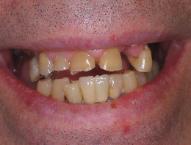

From a cosmetic perspective, one of the most

difficult procedures is to replace a single broken

front tooth with a crown.  Color, size shape and

subtle characterization of the crown have to

match the other teeth to functionally and

cosmetically recreate a natural looking tooth.

Before

Completed crown